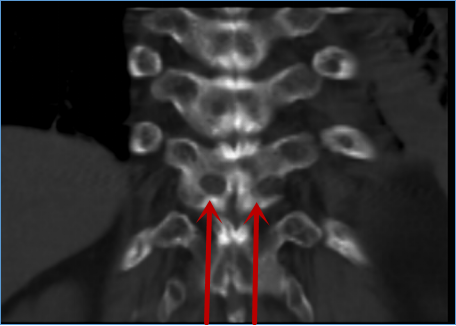

陈远明主任再次通过细致的查体、询问病史,全面的评估病情后提出症状与腰椎病变的影像学表现不吻合,“真凶”可能“另有其人”。经完善胸椎相关检查后,终于发现原来罪魁祸首是胸椎胸11/12黄韧带肥厚、钙化,压迫硬膜囊造成的胸椎管狭窄症。

穿刺入路